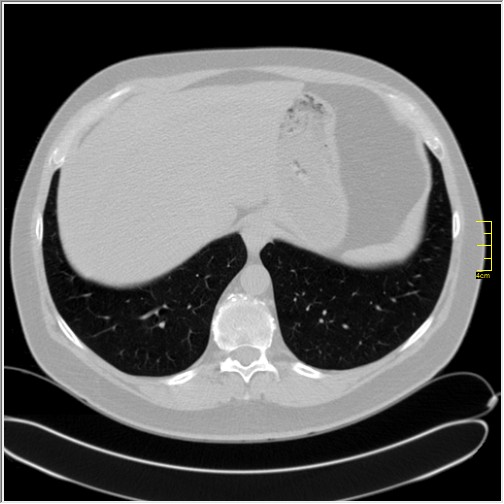

Četiri dana kasnije. Isti pacijent dolazi sa istim pulmologom. Situacija je sada sasvim drugačija. Temperatura 39.5 C. Saturacija 92. Laboratorija daleko gora. Uradim CT pluća. Ovo je izašlo.

Severity score 15/25. Pacijent je upućen na bolničko lečenje.

Ono što zbunjuje, a to se ponavlja zadnjih 10 dana, je da fibroza nastupa u progresivnoj fazi, znači na početku bolesti. Toga nije bilo do sada. Sledećih dana ću o tome.

Ovo je samo 4 dana. Od zdravlja do teške bolesti. Pacijent je 45 godina starosti, očigledno nije povećane težine, kaže za sebe da je bio sportista. U anamnezi nije naveo nikakve bitne bolesti.